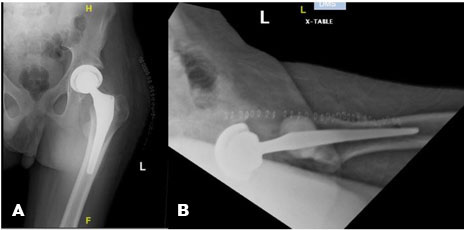

Initial radiographs of the left hip demonstrated a slipped capital femoral epiphysis (SCFE) and evidence of skeletal immaturity (Figure 1A and Figure 1B). The patient’s physical exam was significant for mild tenderness of the left hip, moderate pain with passive internal and external rotation of the hip, and inability to flex and extend the hip due to pain. Neurological and vascular exams of the left lower extremity were within normal limits.

Figure 1: (A and B) Anterior-posterior (AP) pelvis and lateral hip radiographs demonstrating a SCFE in a skeletally immature patient.

On hospital day two the patient was taken to the operating room for open treatment of the left SCFE with in situ screw fixation. Prior to surgery a discussion was had regarding use of a Femoral Neck System for fixation; however, given the large slip angle, fixation with cannulated screws was decided upon. A single 60 mm × 7.3 mm cannulated screw was used for fixation and its placement confirmed on multiple intra-operative fluoroscopic images (Figure 2A and Figure 2B). The patient’s post-operative course was uncomplicated and he was discharged home on post-op day one with home physical therapy. He was made partial weight bearing on the left lower extremity for four weeks before transitioning to full weight bearing. The patient was highly recommended to follow up with his endocrinologist for continued management of his hypopituitarism as well as for monitoring of his overall bone health.